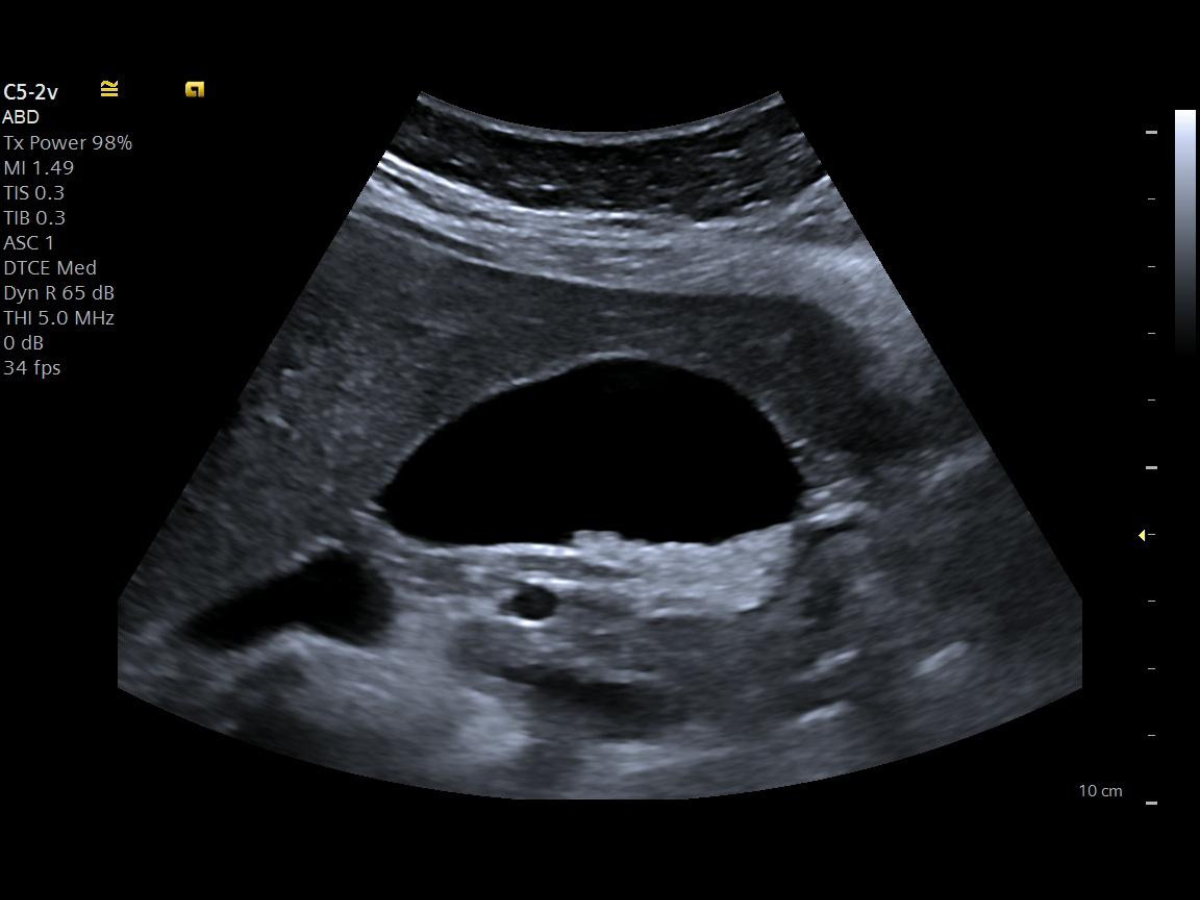

Klinische Beispielbilder

Bildquelle: Siemens Healthineers – ACUSON